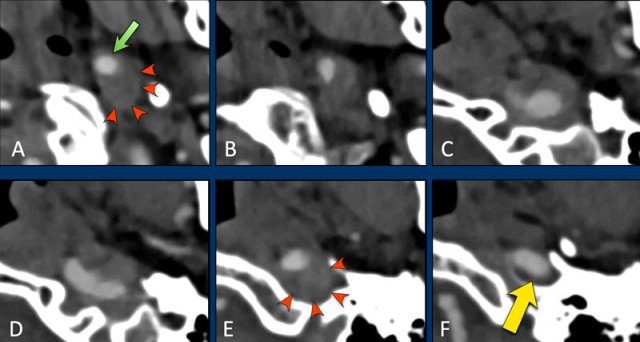

A dissection stops at the skull base

This patient has a carotid

dissection.

In A we see the compressed lumen in

an eccentric position (green arrow).

The diameter of the ICA is enlarged

by the intramural hematoma (red arrowheads).

When we follow the ICA cranially, the

dissection continues up to image E (arrowheads).

At the level of the skull base, where

the ICA enters the carotid canal (vertical petrous segment) , the dissection

stops and the ICA has a normal appearance (yellow arrow).